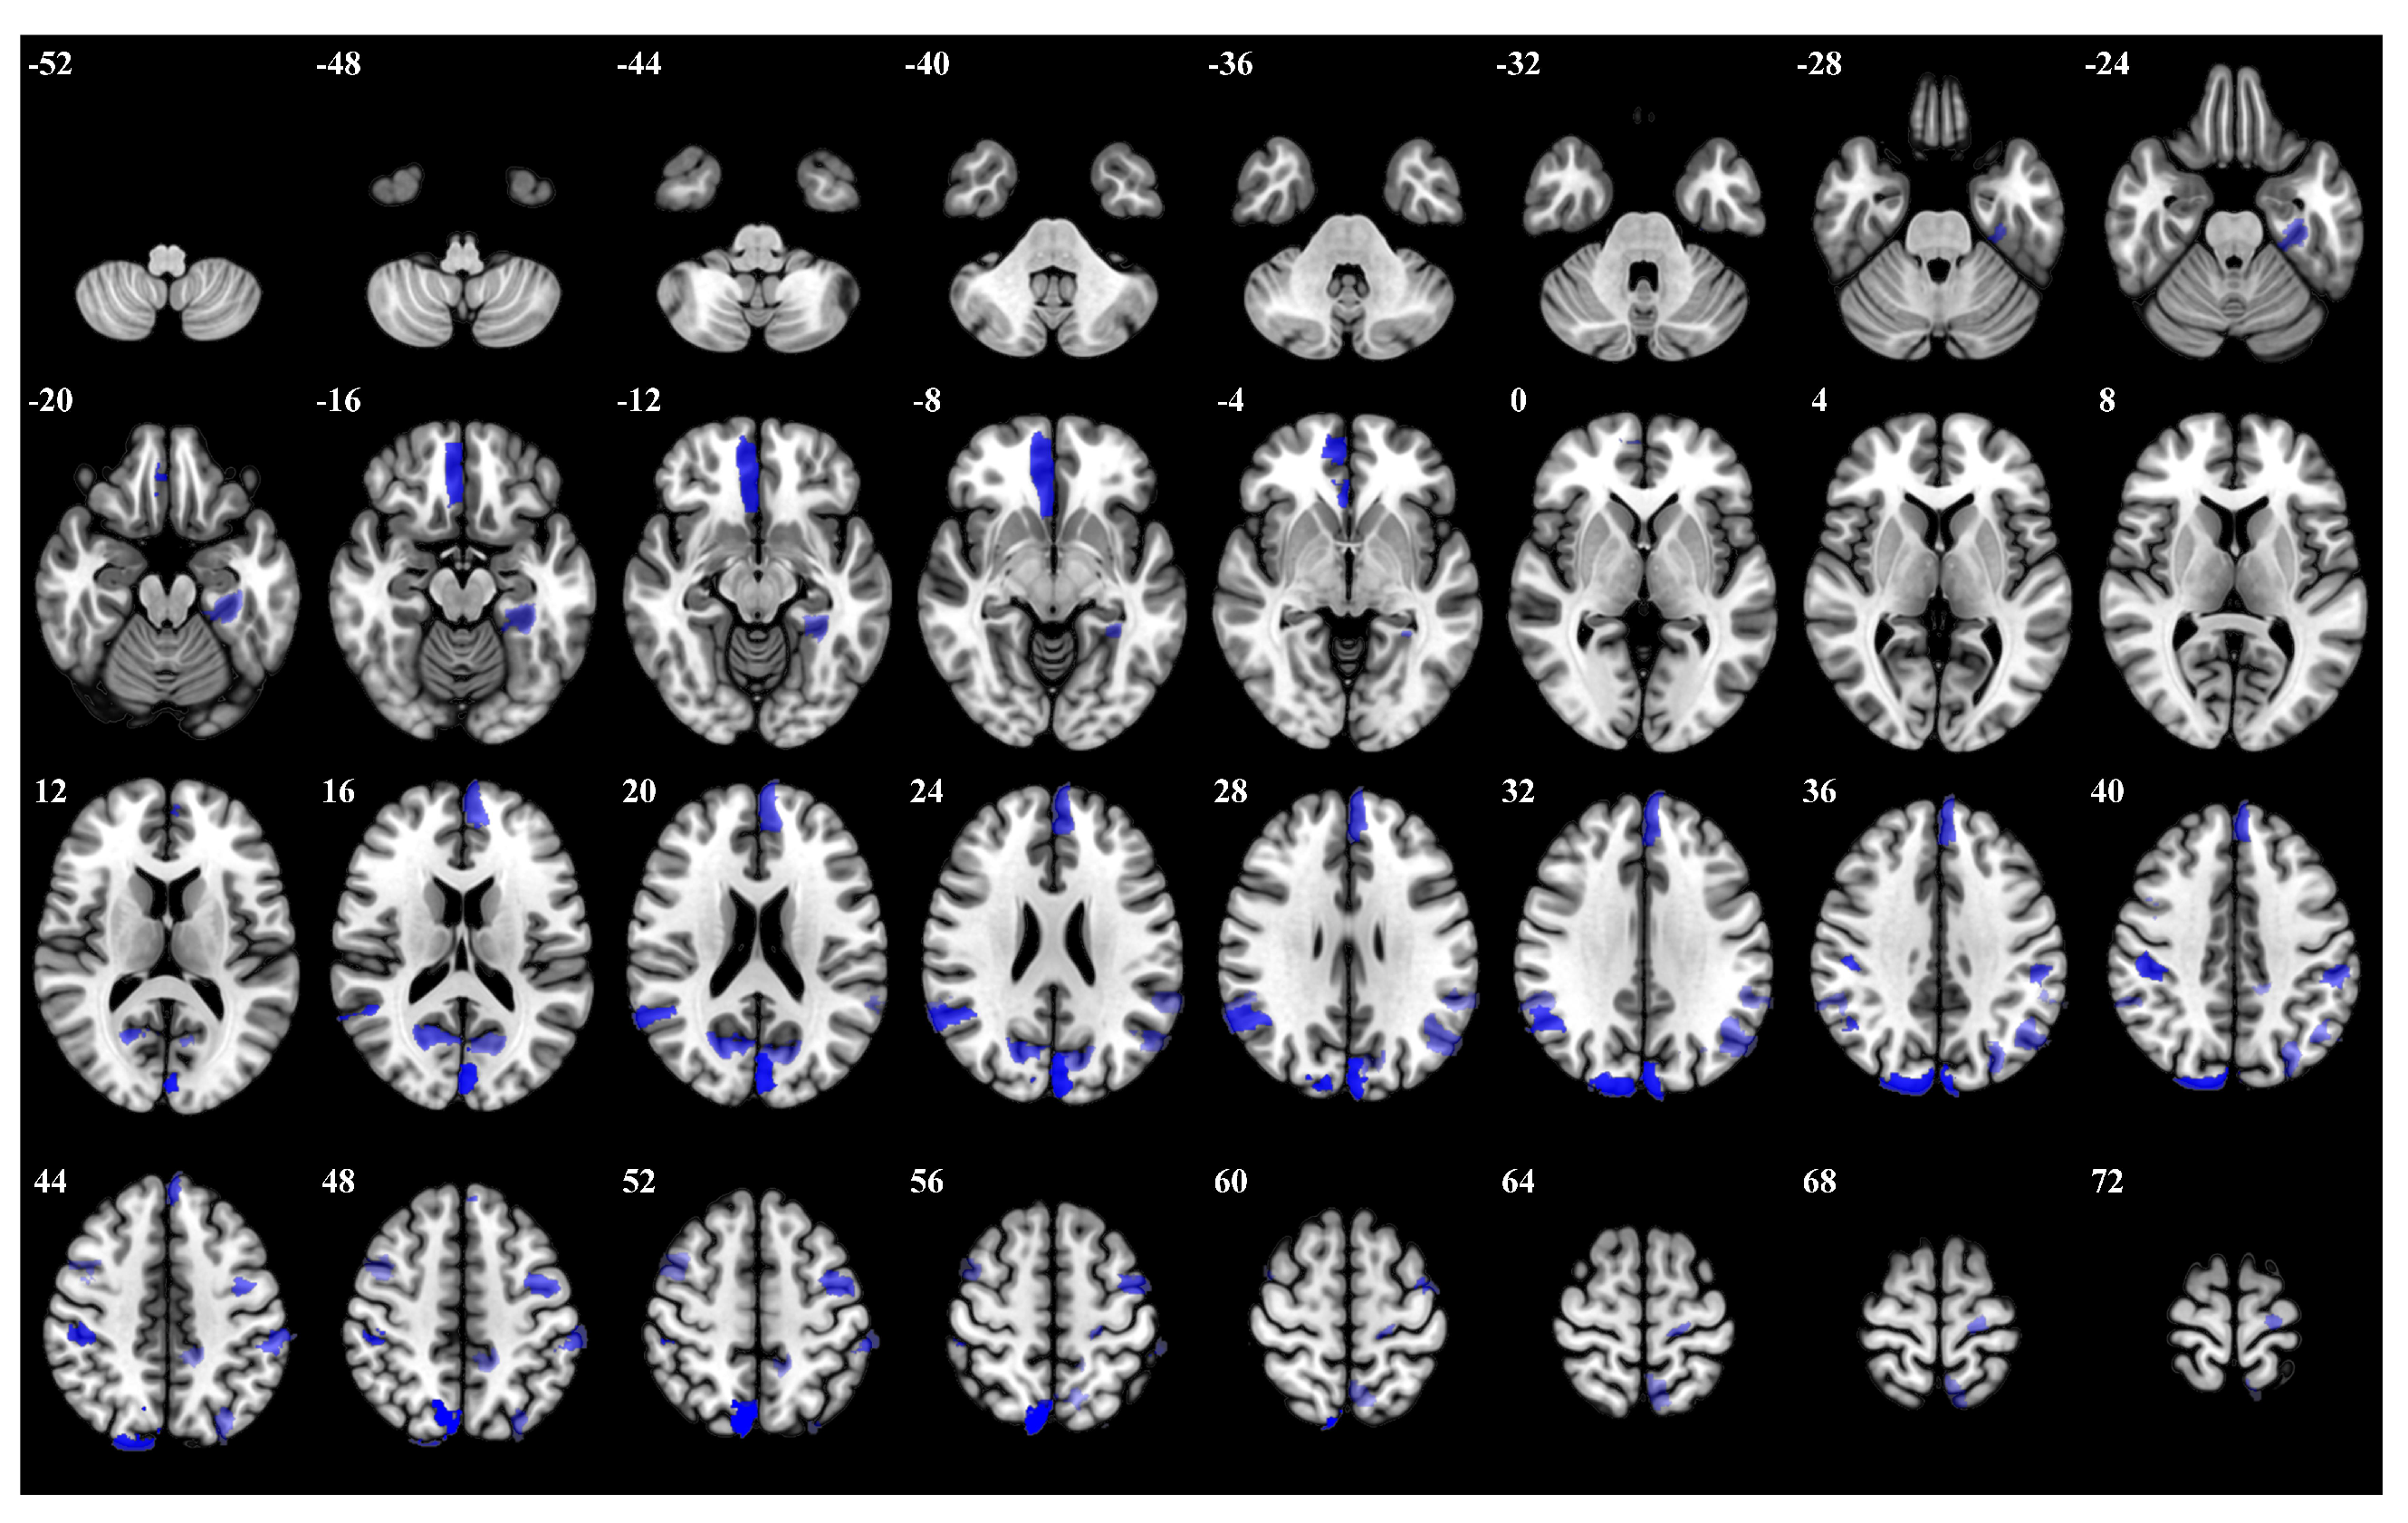

In the 1-back task, participants were required to respond whenever the current stimulus matched the one presented immediately before it. Left hemisphere regions demonstrated prominent activation, including Left Hemisphere Default Precuneus Posterior Cingulate Cortex 3 and Left Hemisphere Dorsal Attention Posterior 15. Furthermore, left hemisphere regions such as Left Hemisphere Frontoparietal Control Parietal 4 and Left Hemisphere Frontoparietal Control Parietal 1 showed significant involvement. The top 5 percent of the most influential ROIs for the 1-back task is visualized in Figure 6, and Table A2 offers specific details on the brain regions.

Figure 6.

The top 5 percent of the most influential ROIs for 1-back, with higher opacity indicating higher influence weights.